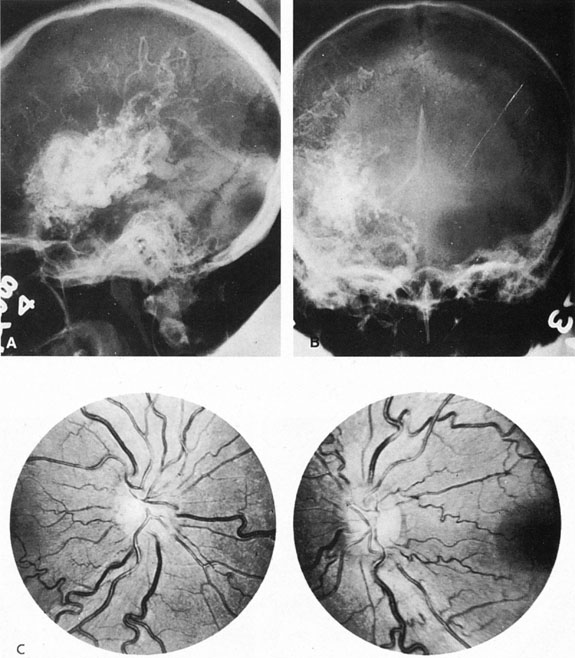

Of particular interest are those AVMs that involve the occipital lobe (Fig. 9). The clinical differentiation of migraine from a cerebral AVM was previously regarded as difficult because the clinical features of occipital lobe AVMs include visual phenomena or headaches. However, in most cases the clinical distinction is possible. In 26 cases with occipital AVM, two distinct syndromes were defined in 18 patients: occipital epilepsy and occipital apoplexy.73 Focal seizures with occipital malformations consist of elementary visual sensations similar to the phenomena evoked by direct cortical stimulations. When seizure activity occurs in the striate cortex (area 17), the patient usually reports sensations of moving lights in the right or left homonymous fields. The sensations are poorly formed, episodic, usually brief, sometimes colored, and unassociated with the angular, scintillating figures so characteristic of migrainous cortical phenomena. Epileptic discharges from areas 18 and 19 cause photopsias that are unlikely to remain stationary and to flicker rapidly. The epileptic photopsias usually last only seconds; occasionally they last for a few minutes before the onset of a generalized seizure. In other instances only the brief visual episodes occur without spreading to produce a generalized seizure. Momentary dimming or blindness in one or both homonymous fields may be experienced with seizure activity in the occipital areas.

Fig. 9. Carotid arteriogram of an occipital lobe arteriovenous malformation (AVM). Lateral (A) and frontal (B) projections demonstrating a small occipital AVM (arrow). The patient was a 23-year-old woman who presented with severe apoplectic unilateral headache, total left homonymous hemianopia, and mild nuchal rigidity. Despite xanthochromic cerebrospinal fluid, she was initially diagnosed elsewhere as having migraine. An AVM was successfully resected, and a small occipital lobe hematoma was removed.

Occipital apoplexy results from hemorrhage and hematoma formation within the occipital lobe and is characterized by sudden severe headache and homonymous visual field loss. Homonymous hemianopia is the most important sign produced by vascular malformations of the occipital lobe. Compression and necrosis of visual pathways by an intracerebral hematoma are the principal mechanisms. Usually the hematoma is large and tends to split or dissect longitudinally through the white matter of the occipital lobe. The effects of compression may be reversed by prompt, surgical evacuation of the hematoma.73 With hemorrhage into one occipital lobe, hemianopia in the visual field of the contralateral normal occipital lobe may develop, producing total blindness that can last for several days. The rapidly expanding hematoma may shift the damaged hemisphere anteriorly, or across the midline, with downward herniation of the uncus through the tentorial incisura. This shift compresses the posterior cerebral arteries and accounts for bilateral occipital lobe dysfunction. Arrest of function in the undamaged occipital lobe may be due to an interhemispheral inhibitory phenomenon termed diaschisis. Visual field defects with occipital AVMs are regularly due to hemorrhage and hematoma formation. Congenital arteriovenous malformations can occupy the entire occipital pole (the macular projection area) for decades without producing visual field defects.